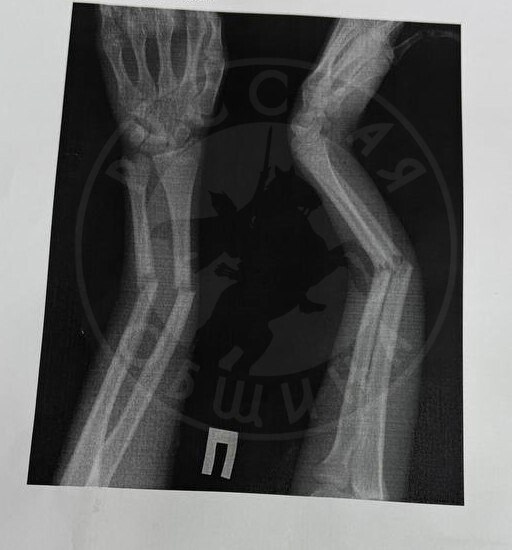

В нижнекамской школе №6 произошел инцидент между учениками. Об этом сообщили в группе «Русская Община | Набережные Челны» во «ВКонтакте». Как отмечает автор сообщения, мальчик подошел к однокласснице и во время разговора схватил ее за руку. После дернул на себя и повалил на пол. Девочка, как уточняется в посте, получила закрытый перелом обеих костей правого предплечья. Кроме того, у нее сильный эмоциональный стресс.

Фото: vk.com/rusobshinanchelny